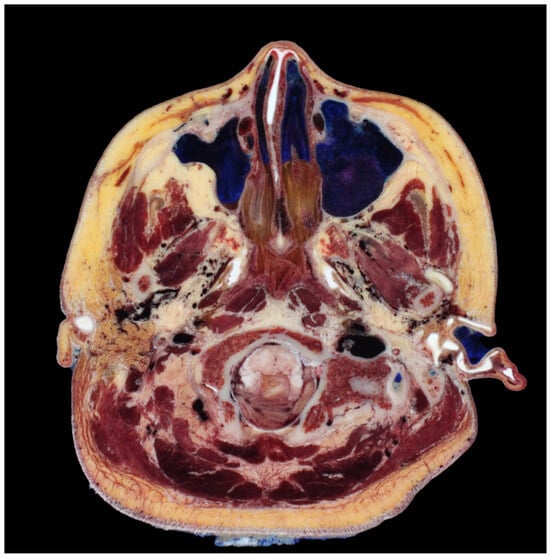

Moreover, the use of steel needles or cannulas faces limitations in their ability to be easily bent beyond a certain extent to match the curvature of this region [26]. Changing the direction of advancement after raising the end of the needle or cannula upwards is also challenging, particularly in the area near the ears. The lateral face near the ears presents tough and firm skin and connective tissues, a thick SMAS layer, and a sparse deep fat layer beneath the SMAS. This results in an overall flattened adherence of the skin and tissues compared to other facial regions, making it practically challenging to pass needles or cannulas through and subsequently alter their direction upwards to face downwards, considering the strength of the tissues that need to be lifted (Figure 6).

Figure 6.

Highlights variations in the organization of subcutaneous tissue between the fundamental facial area (A) and the parotid region (B), potentially indicating differences in tissue composition or structure.